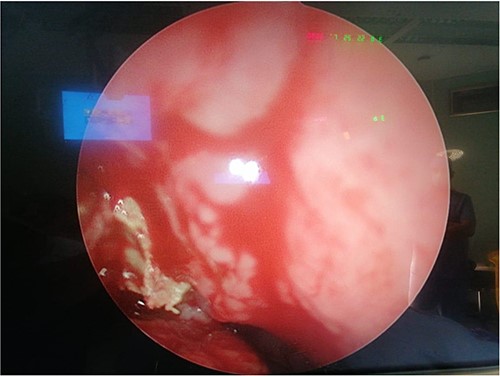

The patient underwent FESS + STP. Intra-operative examination showed mucopurulent discharge coming from the right nostril, so a swab was taken and sent for culture and sensitivity. Following that, 0° rigid scope revealed the presence of granulation tissue filling the right nostril and a query foreign body that were removed and sent for histopathology (Fig. 2). Septoplasty was done and there was also granulation tissue originating from right posterior septum which caused septal perforation. Moreover, examination of middle meatus (MM) and maxillary antrum also showed granulation tissue with mucopurulent discharge, in which maxillary sinus was opened and cleaned along with anterior and posterior ethmoid sinuses (Fig. 3). The pathology report revealed the presence of acute inflammation and bacterial colonies morphologically suggestive of actinomyces species. She was started on Augmentin 1 gram BID, with nasal irrigation and she was referred to infectious diseases service and they continued Augmentin treatment 6 months. Patient reported improvement of her symptoms.

Fungal material after removal from middle meatus (thought to be foreign body).

Intra-operative photo shows fungal material with pus discharge in middle meatus.